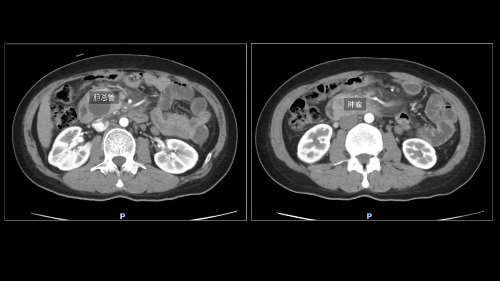

胡女士做完肝功能检测、腹部CT等检查后,结果显示——

“胆总管下段显示不清,可疑软组织密度影在其内,同时还伴有肝内外胆管的扩张及胰腺炎表现;上腹核磁提示壶腹部有一个肿块,肝内外胆管显著扩张,胰管也有增宽,考虑壶腹恶性肿瘤……”

壶腹占位

是导致背痛和尿色深黄的主要原因

可能得了非常严重的恶性肿瘤性疾病

△胡女士拍片结果